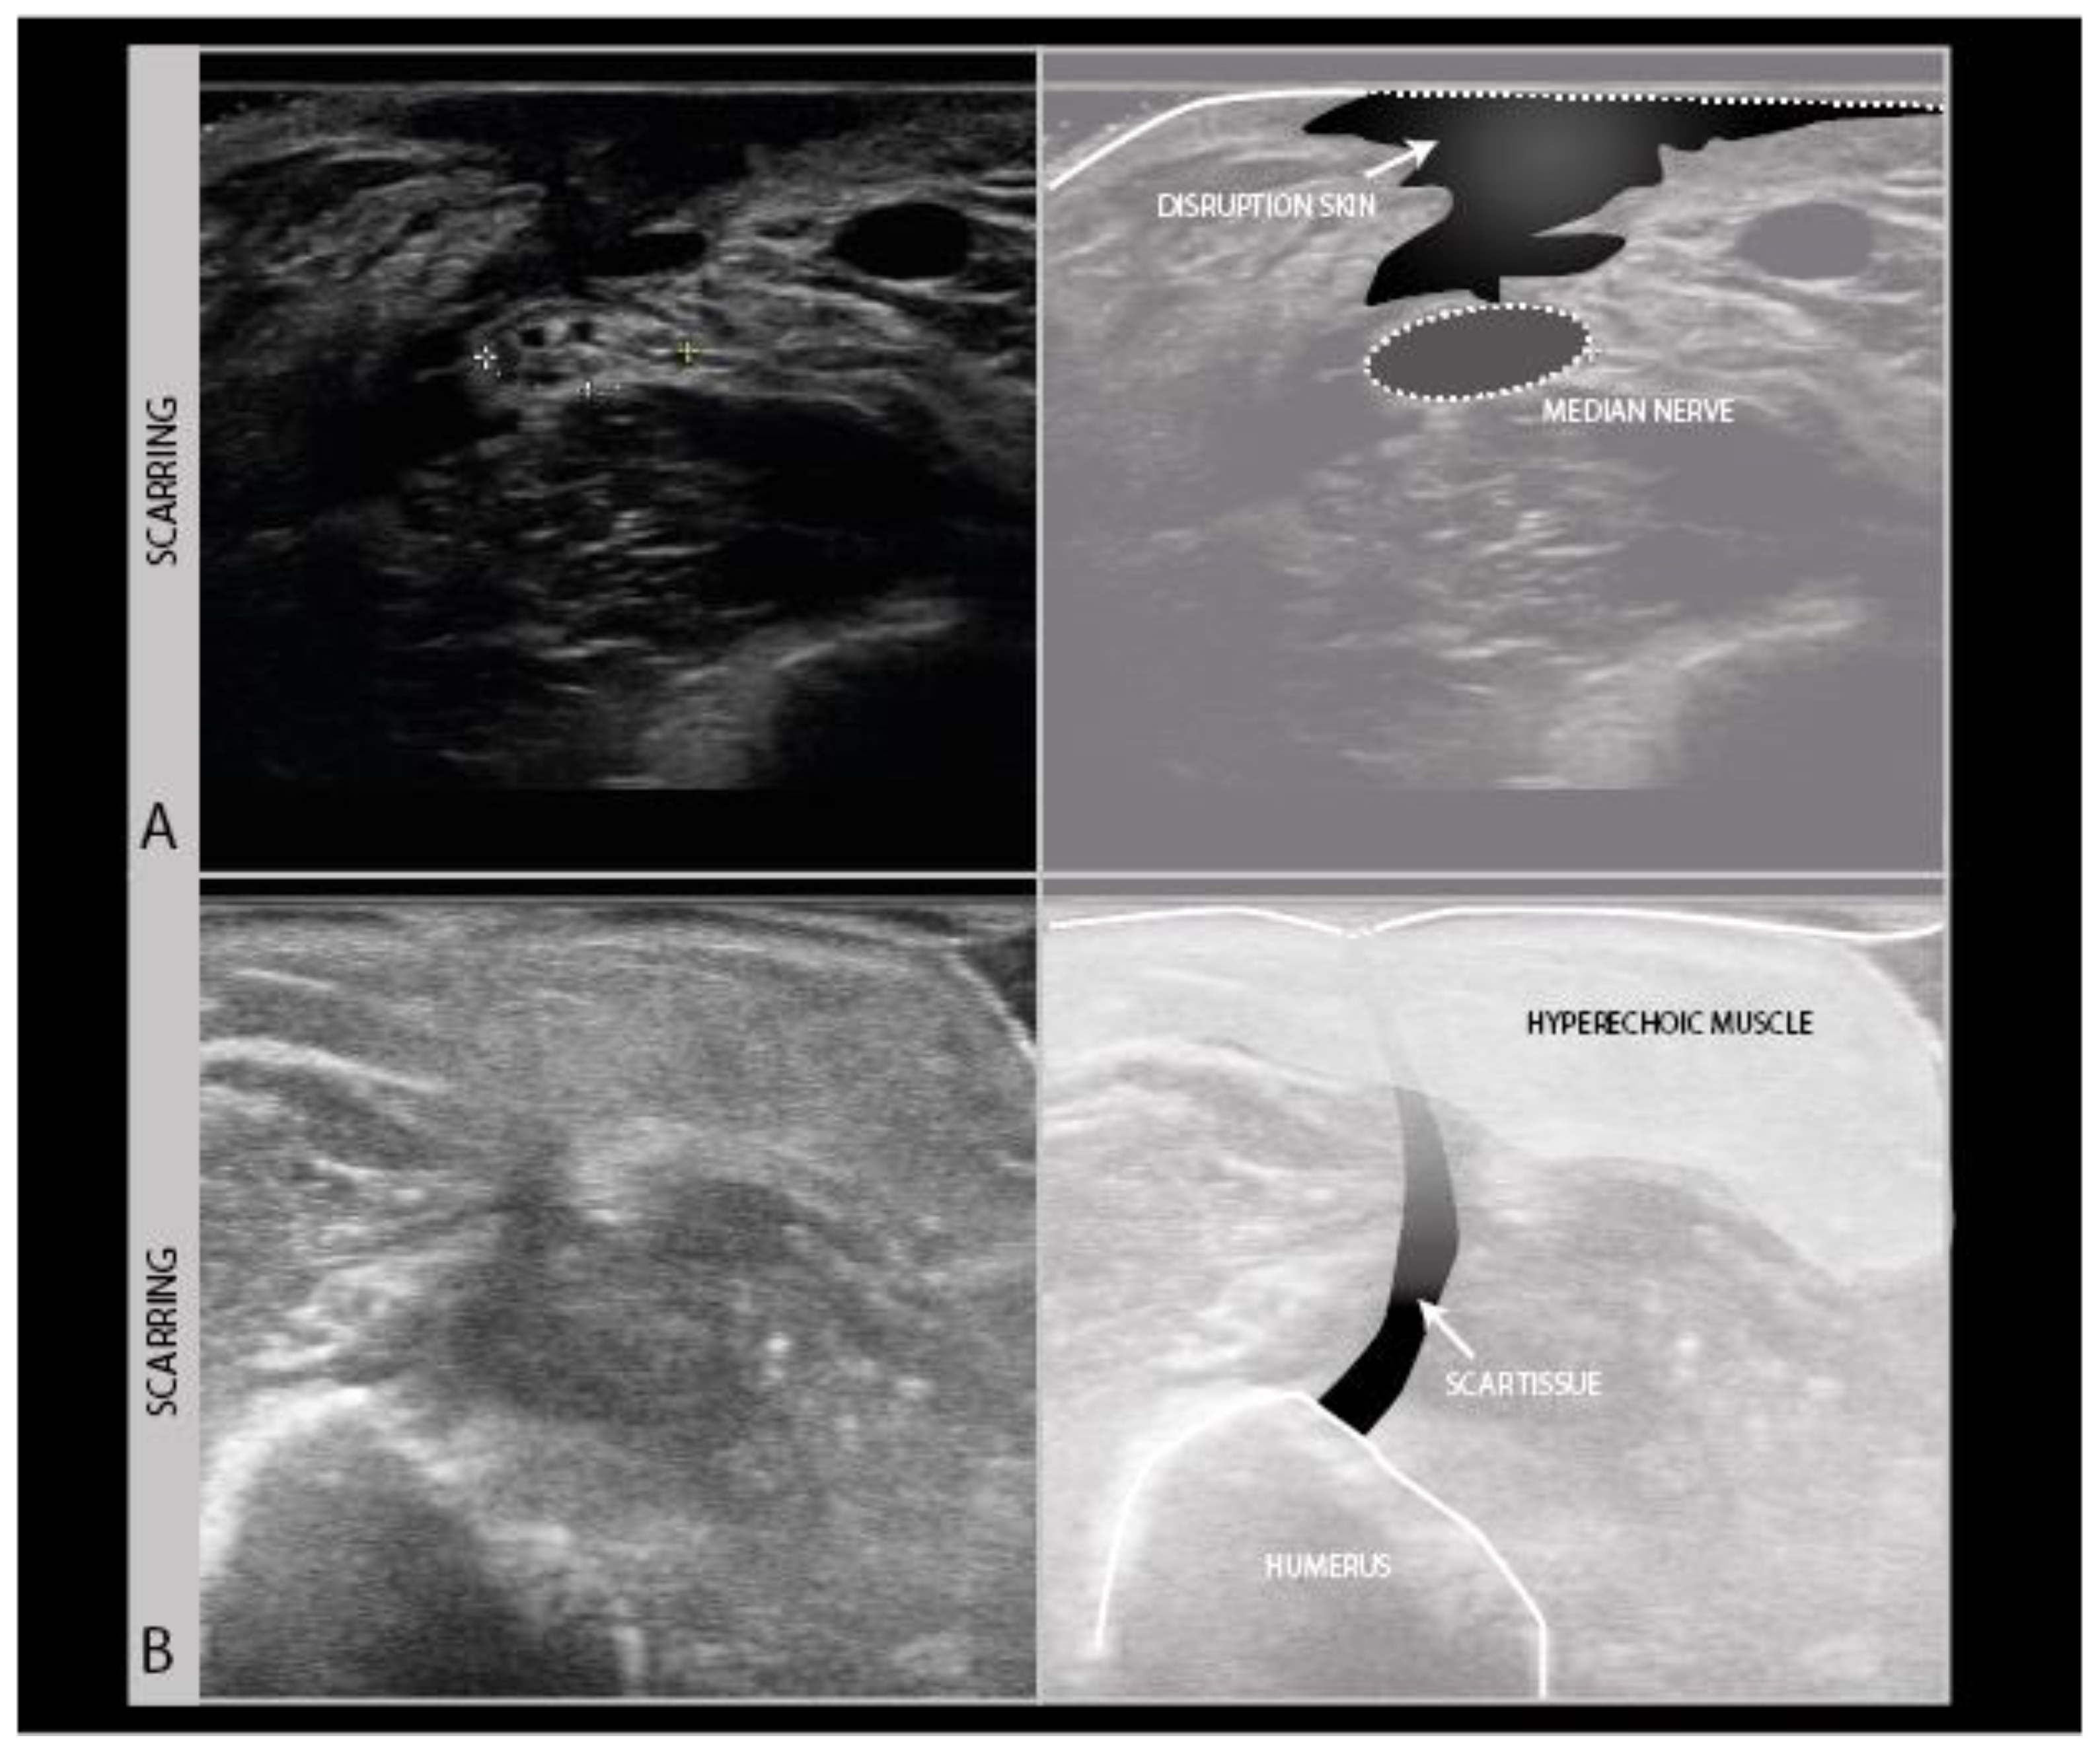

During the ultrasound scanning of nerve trauma patients, it is not only important to look at the nerve itself, but also to scan its anatomical surroundings for any abnormality that may impact on nerve recovery or pose an additional problem for the patient. The most commonly observed abnormality in trauma is scarring. As scars often run perpendicular to the skin surface, they are hard to visualize well with ultrasound, as the soundwaves travel parallel to the lines of the scar and almost nothing gets reflected back to the probe. Scars therefore show up as vaguely defined hypoechogenic longitudinal lines in the skin, subcutaneous tissue and fascia (Figure 8A), sometimes only visible by the interruption of other architectural features in those layers (Figure 8B).

Figure 8.

Examples of scarring of the skin and subcutis. Severe disruption of skin and subcutaneous tissue showing as a craggy hypoechogenic region over a median nerve neuroma in continuity in a patient with the piercing trauma of the forearm by a wooden fence (A). Hyperechogenic subcutis and muscle following surgery for an open humerus fracture, with a subtle vertical scar line interrupting the tissue layers (B).

Scarring can also involve the nerve and its connective tissue ensheathing itself (Figure 9A), and can lead to a loss of nerve elasticity and adhesions to surrounding tissues (Figure 9B).

Figure 9.

Persistent median neuropathy with very thick epineurial rim and hypoechogenic, swollen nerve fascicles, in a female patient who underwent 30+ carpal tunnel release surgical procedures (A). Median nerve adhesion in the distal forearm; the superficial epineurium of the nerve is tethered to the flexor carpi radialis tendon sheath directly on top of the nerve (hyperechoic region between the tendon and nerve) (B).